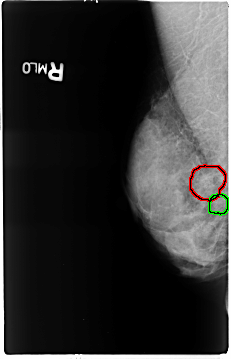

B_3120_1.RIGHT_MLO

FILE: B_3120_1.RIGHT_MLO.OVERLAY

TOTAL_ABNORMALITIES 2

ABNORMALITY 1

LESION_TYPE CALCIFICATION TYPE PUNCTATE-PLEOMORPHIC DISTRIBUTION CLUSTERED

ASSESSMENT 4

SUBTLETY 3

PATHOLOGY BENIGN

TOTAL_OUTLINES 1

ABNORMALITY 2